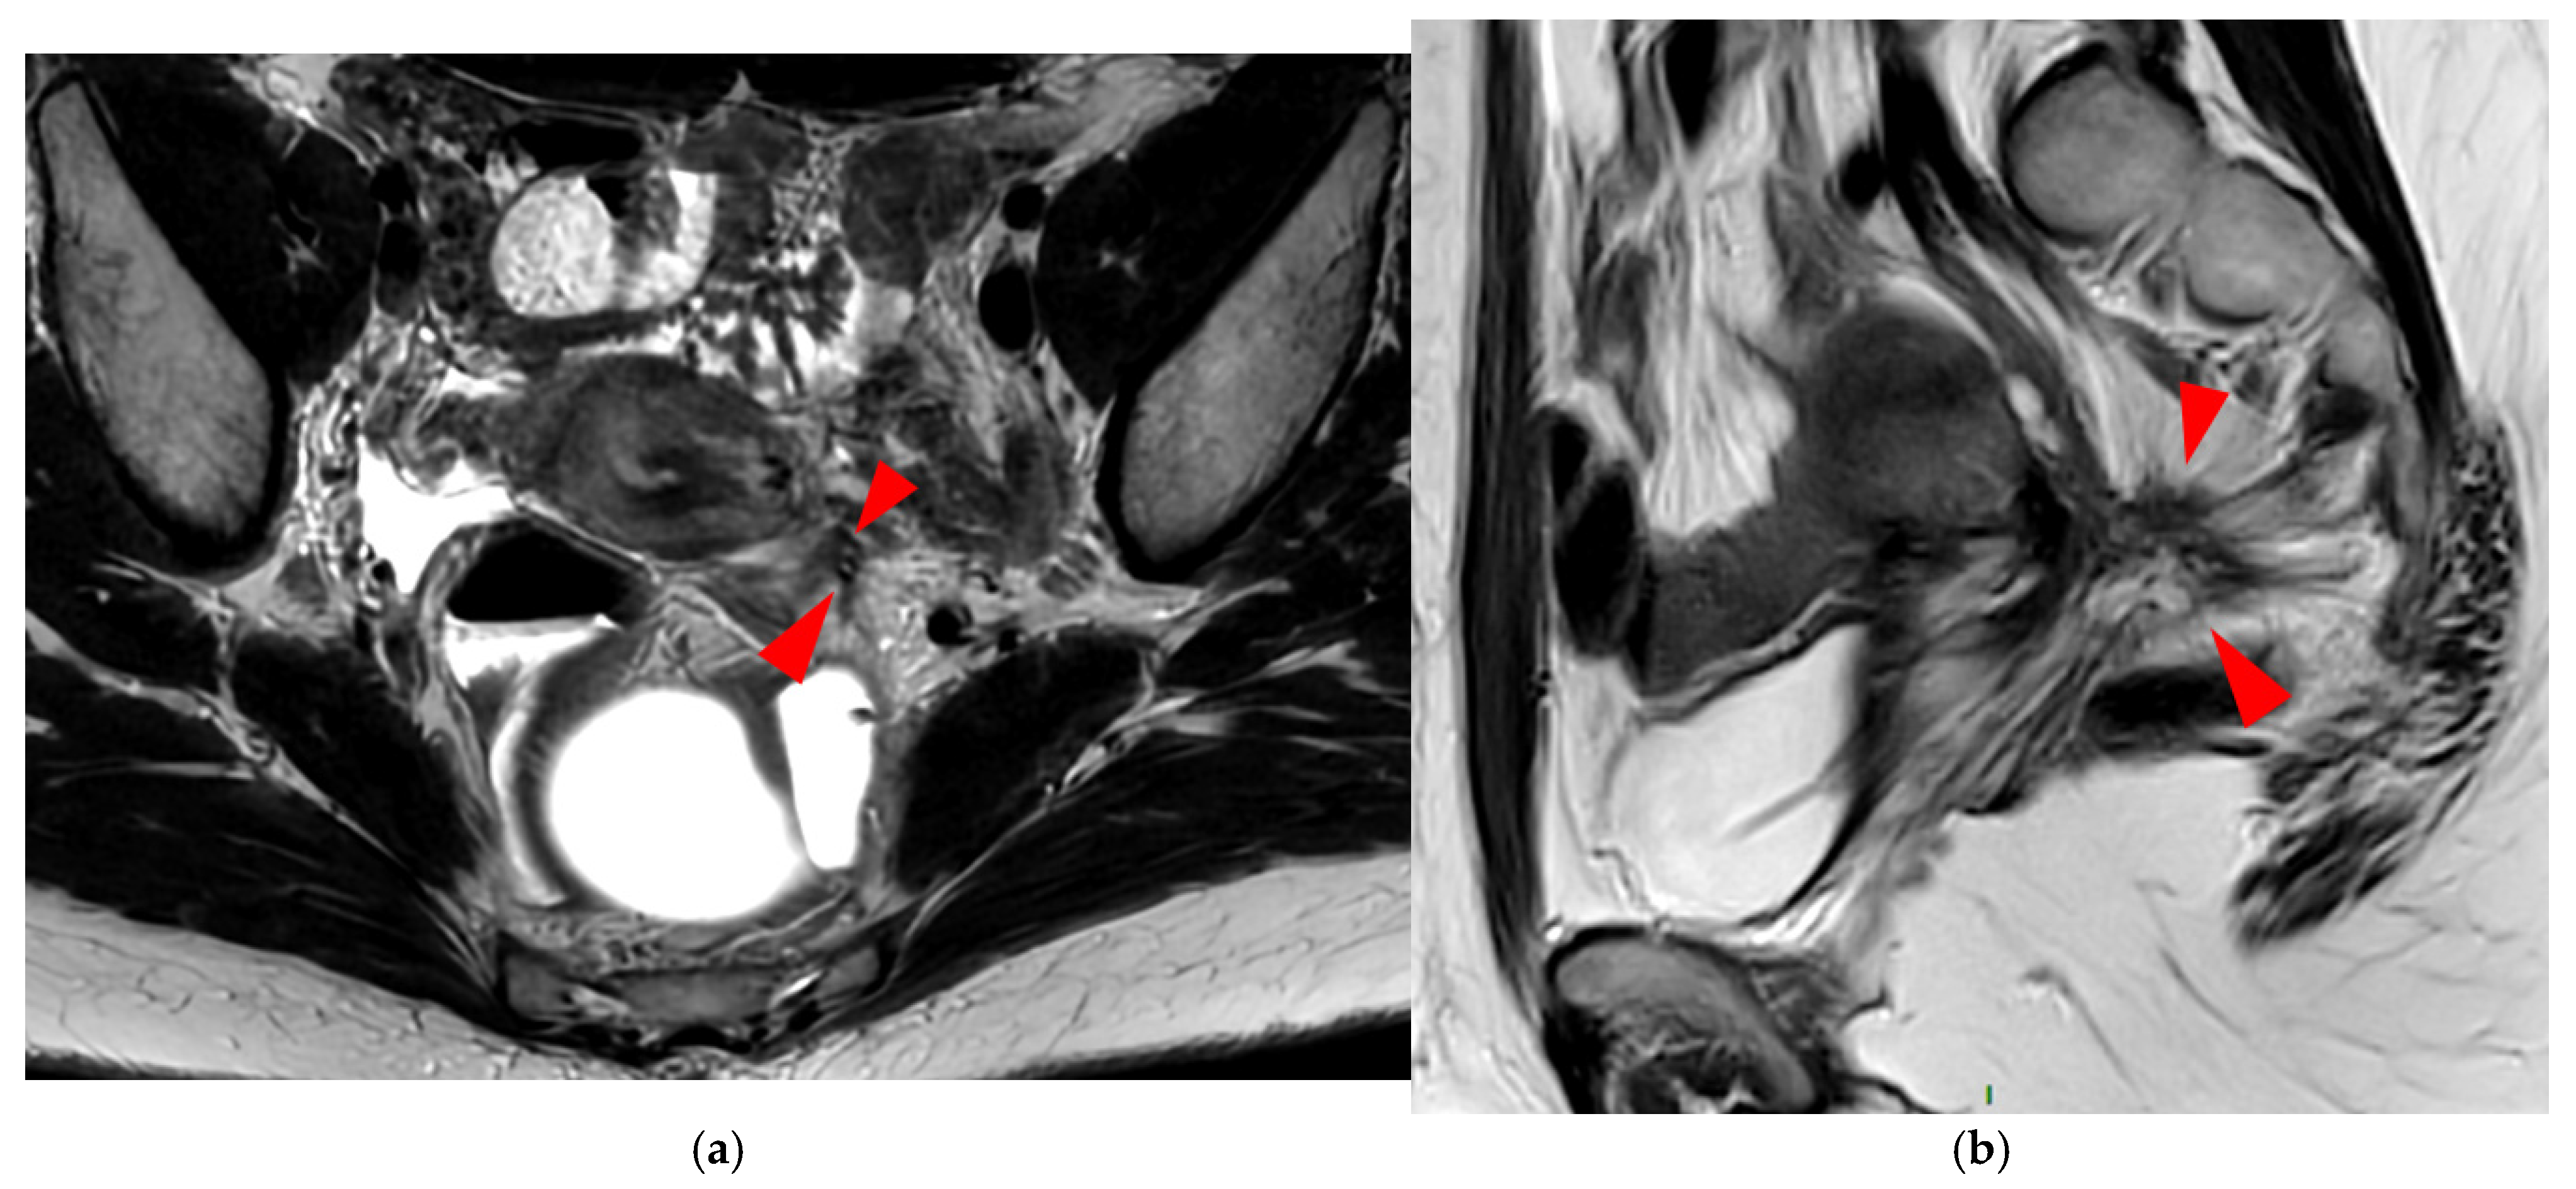

A type 5 USL appears nodular and can be classified either as type 5A or type 5B.

A type 5A USL (Figure 6) is nodular with a smooth contour.

A type 5B USL (Figure 7) is nodular with spiculated margins. A type 5B USL may also display an isolated nodule with microcystic content.

Figure 6. Pelvic MRI scans of two patients with HTD type 5A USLs. (a,b) Sagittal T2WI: nodularity with regular margins (arrows) within the right USL (arrowheads).

Figure 7. Pelvic MRI scans of two patients with HTD type 5B USLs. (a) Patient 1: sagittal T2WI shows a microcystic nodule (arrow) within the origin of the right USL (arrowhead). (b,c) Patient 2: axial (b) and sagittal (c) T2WI show a nodular left USL with spiculated margins (arrow) and a right ovarian endometrioma (arrowhead).